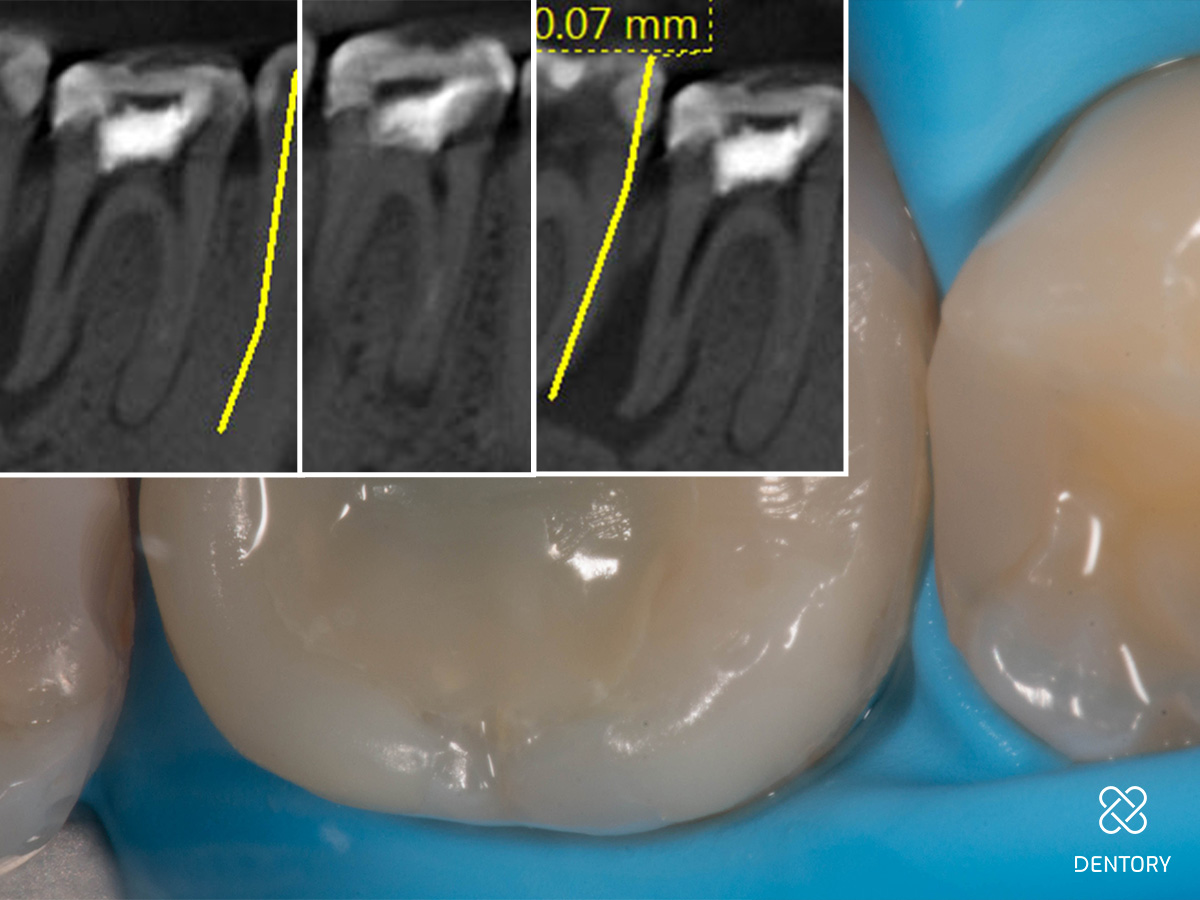

Abbildung 7

Zweite Sitzung: Zentral ist der temporäre Verschluss im Prä-Endo-Aufbau sichtbar.

Abbildung 8

DVT-Ausschnitte nach Entfernung der alten Guttapercha.